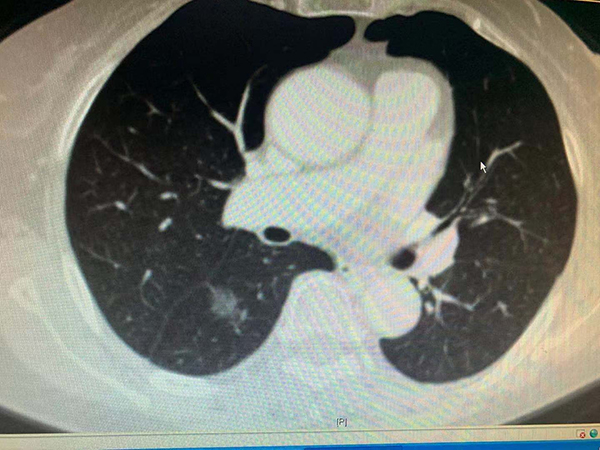

黃淮網(wǎng)  近日,一例81歲老人因進食困難在地方醫(yī)院檢查發(fā)現(xiàn)為食管癌,同時還發(fā)現(xiàn)肺上還有一病灶,性質(zhì)不能確定,因病情復(fù)雜慕名來到徐醫(yī)附院就診。

徐醫(yī)附院胸心外科主任王國祥接診后,仔細(xì)分析發(fā)現(xiàn)肺部病灶也是肺癌,同樣需要切除。患者家屬積極要求同期手術(shù)根治肺和食管兩個癌腫。但患者年事已高,又有冠心病PTCA病史,常規(guī)手術(shù)創(chuàng)傷太大、風(fēng)險高。胸心外科通過網(wǎng)絡(luò)會診,吸取國內(nèi)頂級醫(yī)院的建議,決定利用本院新引進的神器——達(dá)芬奇機器人,在機器人胸腔鏡輔助下,用微創(chuàng)的辦法同期根治兩種病變。

11月14日,在麻醉科手術(shù)室的通力配合下,王國祥主任團隊首先利用機器人的熒光輔助功能精準(zhǔn)切除老人肺癌所在的肺段及腫瘤并最大限度保留老人的正常肺組織,接下來在機器人的輔助下,通過幾個小孔分別切除食管癌、清掃區(qū)域淋巴結(jié),游離病人的胃、并將它提到頸部,在頸部與食管吻合以重建消化道。通過4個小時的努力,成功而安全的完成手術(shù)。